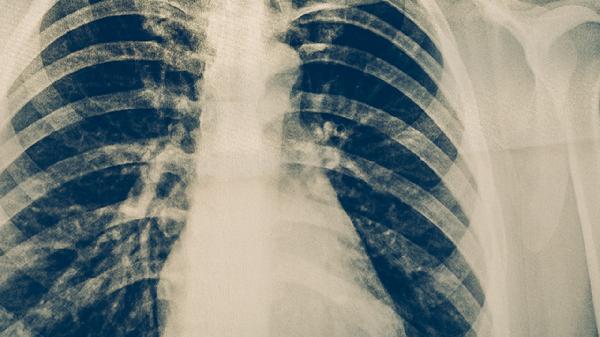

细菌性肺炎通常需要使用抗生素治疗,常见的药物包括阿莫西林胶囊、头孢克肟分散片、左氧氟沙星片、阿奇霉素片和莫西沙星片等。细菌性肺炎是由细菌感染引起的肺部炎症,常见症状有咳嗽、咳痰、发热等,建议及时就医,在医生指导下使用合适的药物。